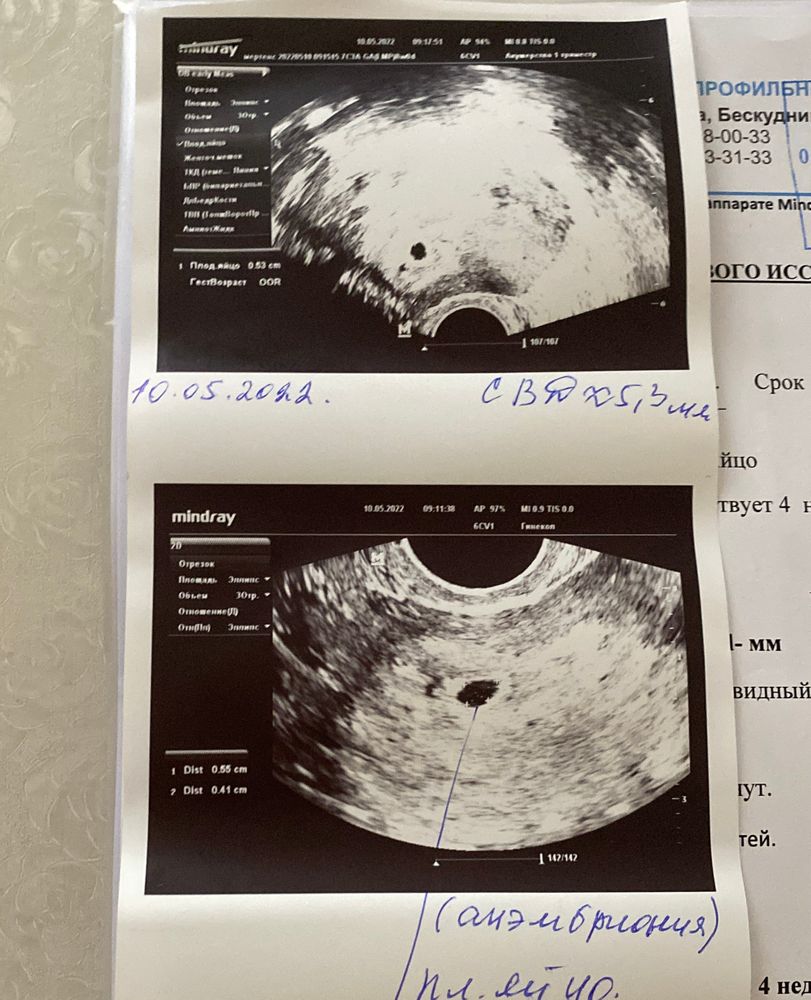

Елена, надеюсь, просто такие диагнозы ставят сразу сходу и надежды не дают. Изображение